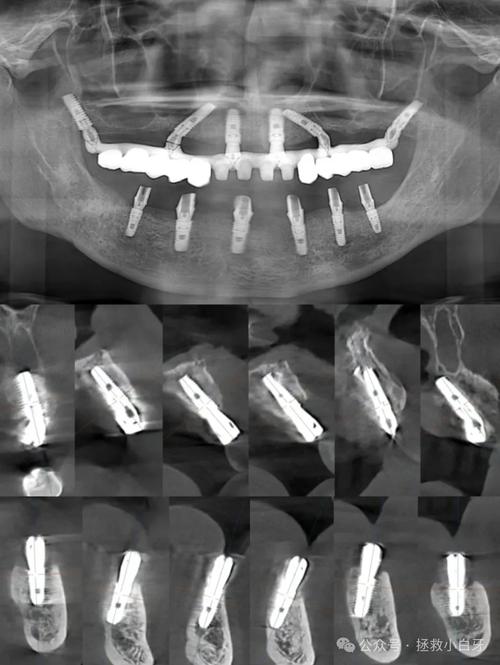

- 精确的手术计划: 需要术前进行详细的CBCT检查和数字化设计,确保种植体植入位置、角度、深度精确无误,为后期修复提供理想条件。

- 术前全面检查: 务必进行详细的口腔检查,包括CBCT(锥形束CT)扫描,评估骨量、骨密度、神经血管位置等,这是制定精准方案的基础。